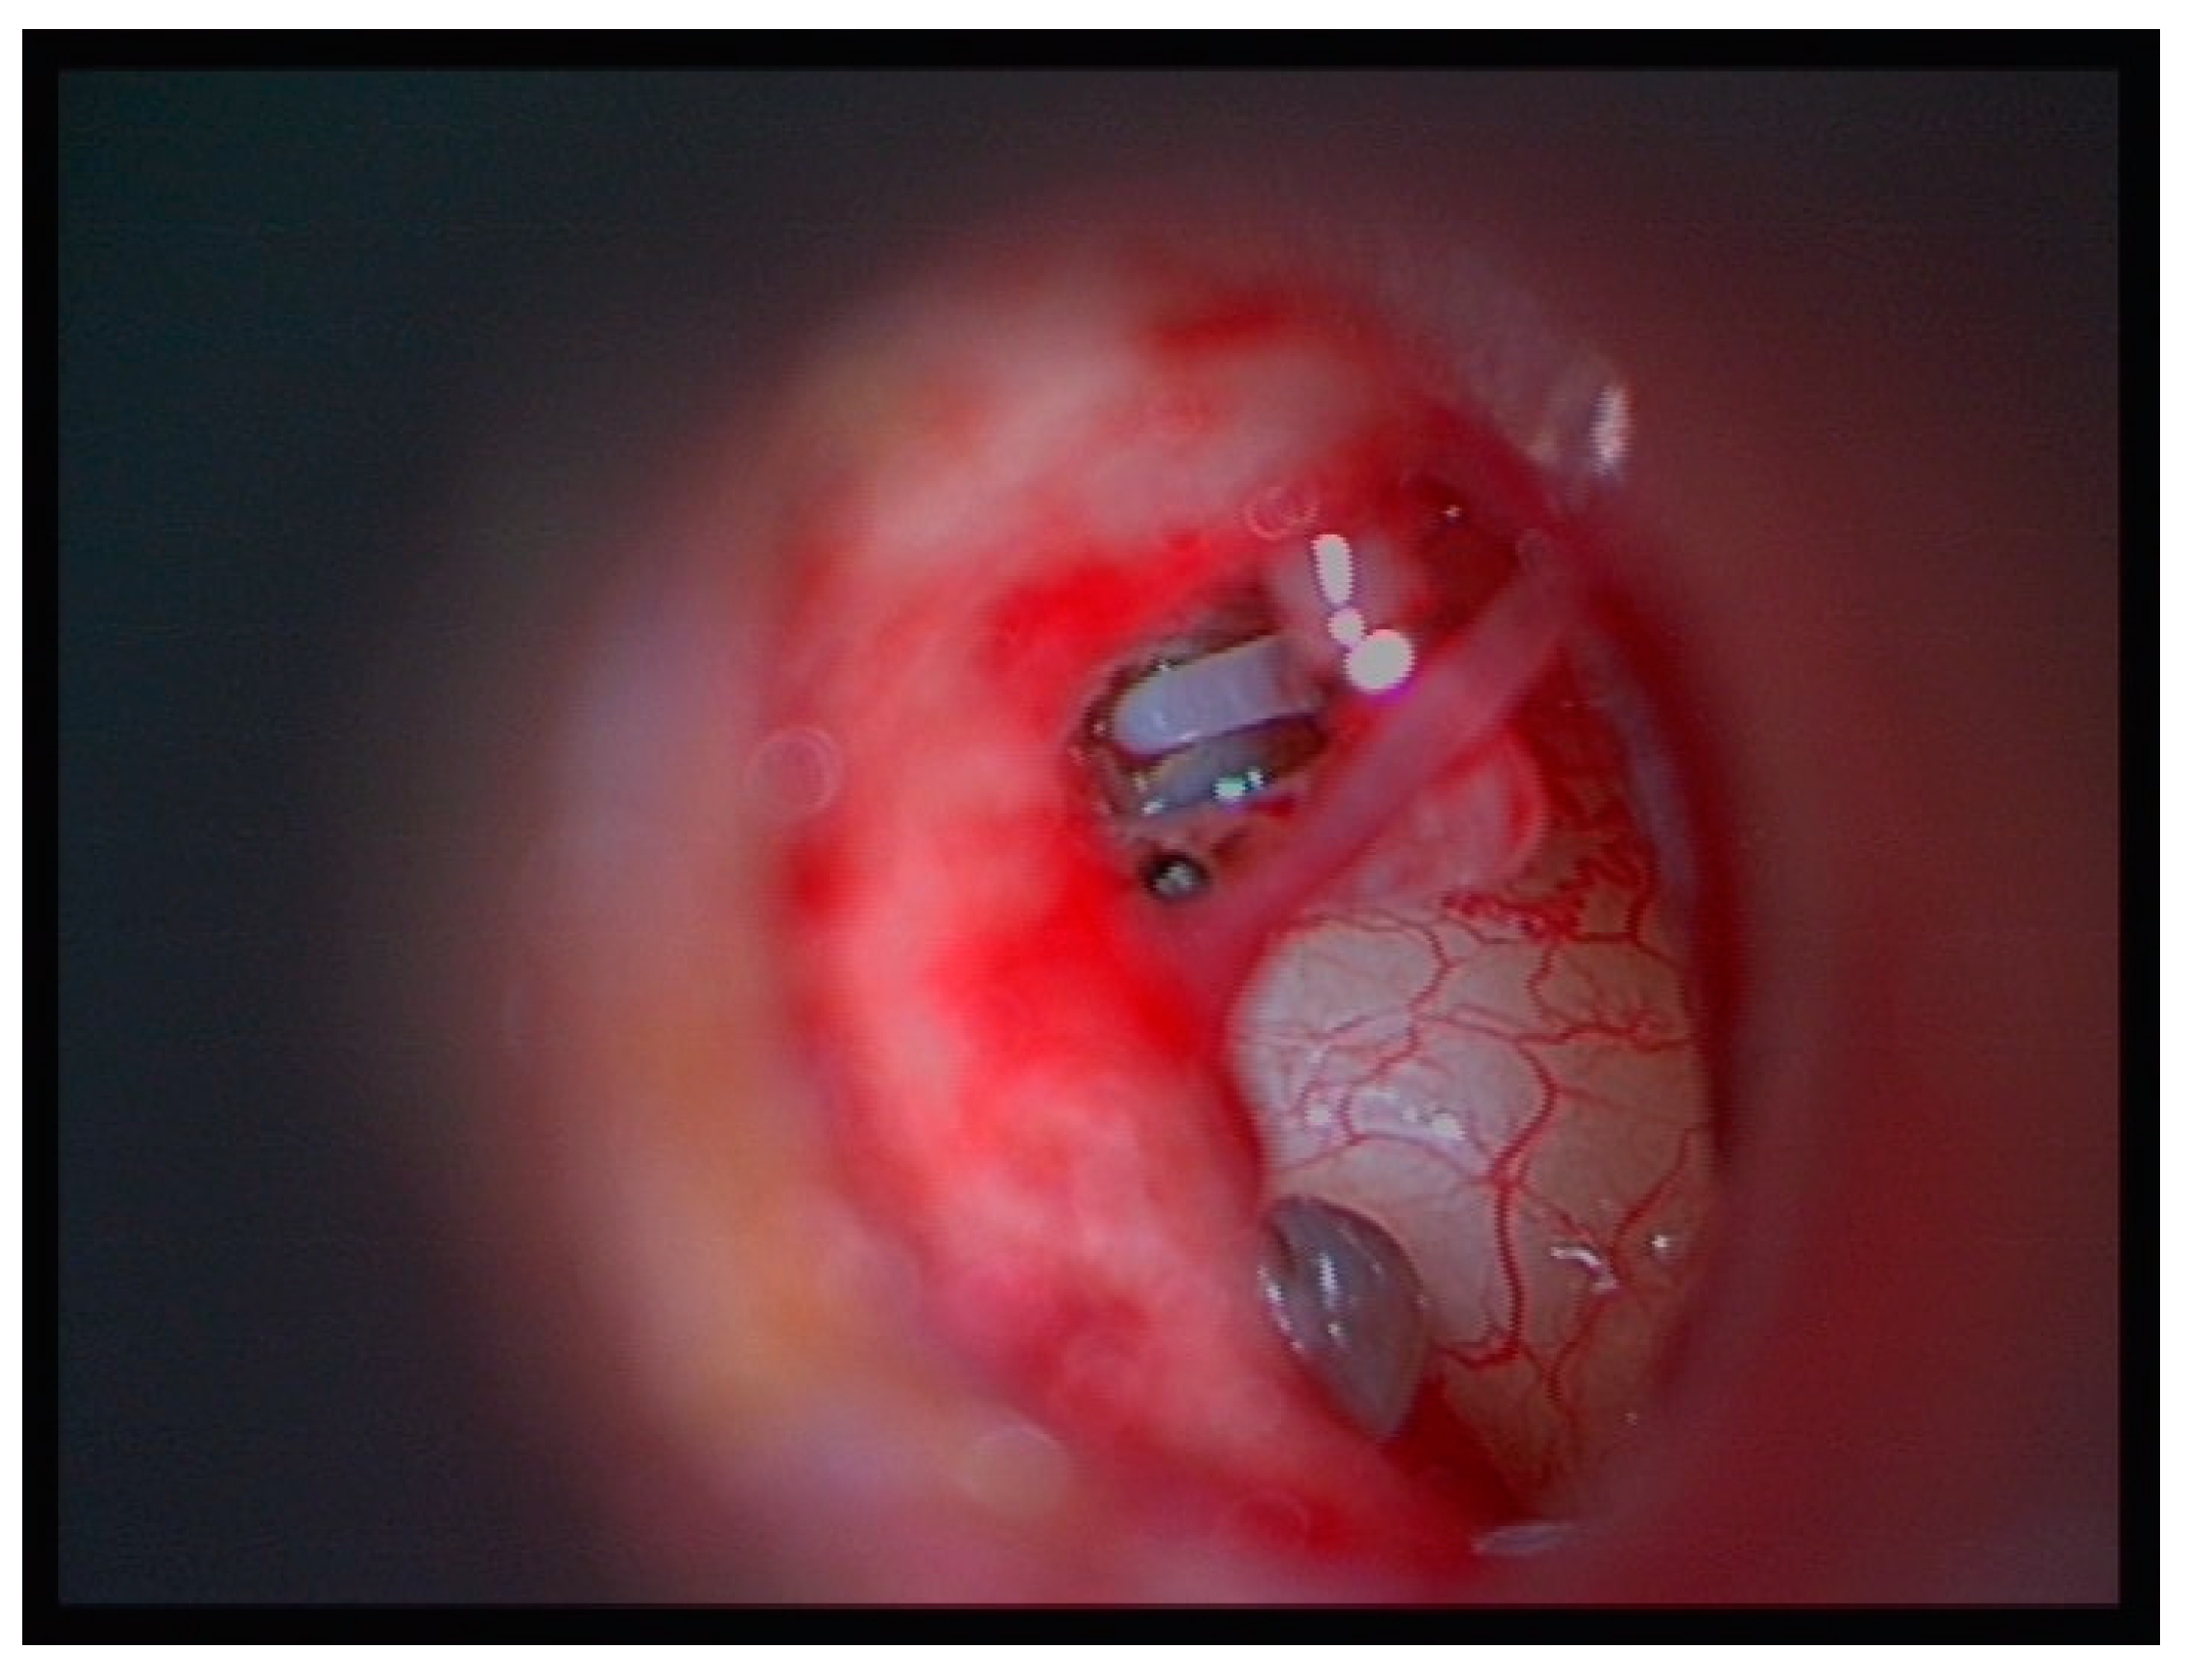

2.4. Surgical Technique